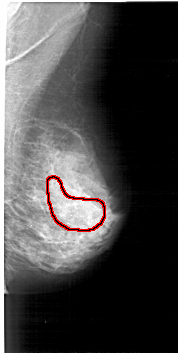

FILE: A_1196_1.RIGHT_CC.OVERLAY

TOTAL_ABNORMALITIES 1

ABNORMALITY 1

LESION_TYPE CALCIFICATION TYPE PLEOMORPHIC-FINE_LINEAR_BRANCHING DISTRIBUTION SEGMENTAL

ASSESSMENT 5

SUBTLETY 5

PATHOLOGY MALIGNANT

TOTAL_OUTLINES 1

BOUNDARY